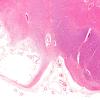

VASCULAR

Small Vessel Disease (3)